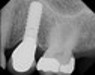

Type of Implants Endosteal (in the bone): This is the most commonly used type of implant. The various types include screws, cylinders or blades surgically placed into the jawbone. Each implant holds one or more prosthetic teeth. This type of implant is generally used as an alternative for patients with bridges or removable dentures.